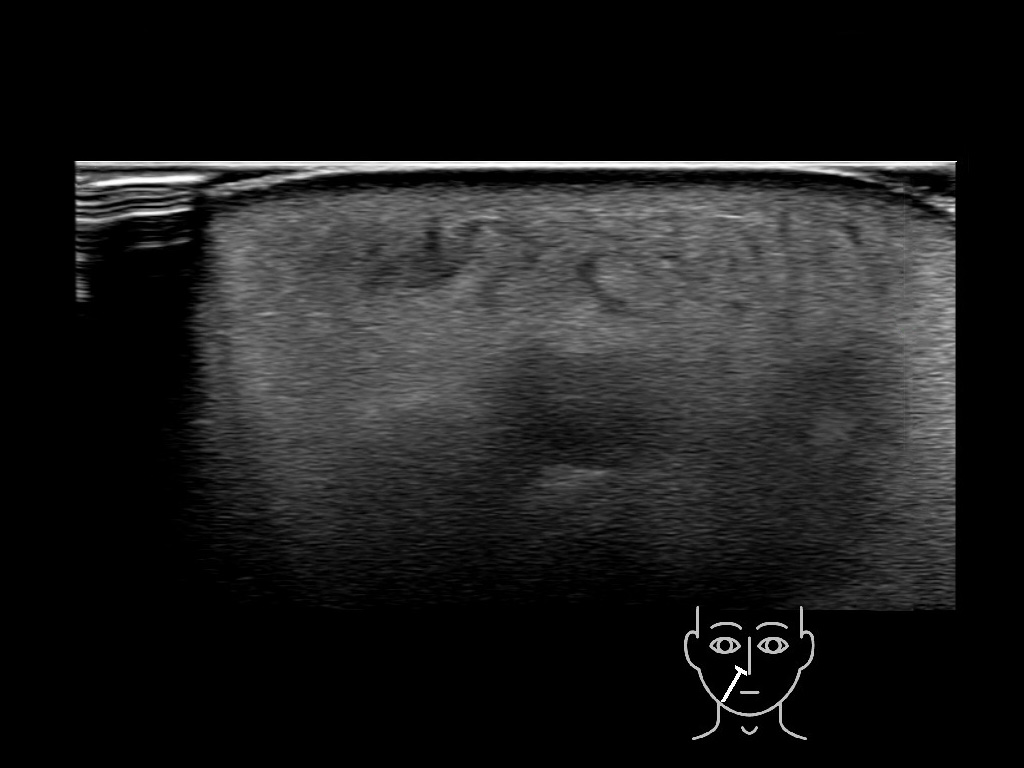

With ultrasound signs of inflammation can be visualized. Edema can be seen as a hyperechoic appearance of the subcutaneous fat, sometimes separated by hypoechoic fluid filled area’s, known as cobblestone appearance. Increased vascularization (hypervascularity) can be seen on colour Doppler. An abscess will appear as a fluid collection appearing as an irregular hypoechoic area with heterogeneous internal echoes and a thickened wall. Posterior acoustic enhancement can be present, and there is vascularity around but not within the mass. Under ultrasound guidance, abscesses can be managed by needle aspirations (18G) under antibiotic cover.

Study the first image to recognize the different layers. If you are sure about the layers, swipe to the second image to view the answer (if applicable).